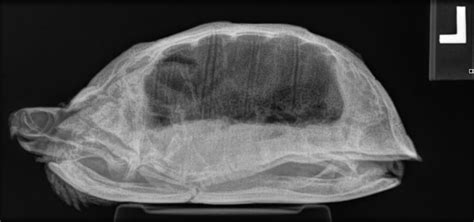

The process involves sending these high-energy rays through the object you want to examine, such as a patient’s body. As the X-rays pass through, some are absorbed or scattered by different materials based on their density. Denser materials, like bones, absorb more X-rays, appearing as white or lighter areas on the resulting image. Less dense materials, like soft tissues, allow more X-rays to pass through, appearing as darker areas. The result is a two-dimensional image that provides a detailed view of the internal structures, and this is what we would call an X-ray. Understanding this fundamental process is essential for grasping how an IITurtle X-ray, or any X-ray machine, functions. The X-ray machine works by emitting X-rays, which are a form of electromagnetic radiation. These X-rays are directed at the area of interest, like a patient’s body. The X-rays then pass through the body. The extent to which the X-rays pass through the body depends on the type of tissues they encounter. When these X-rays hit the detector, an image is created. This allows us to see internal structures, providing valuable information for medical diagnosis. This provides us with the ability to see things we can’t see with the naked eye.

Okay, now let’s talk about how the IITurtle X-ray actually works, looking at it from a side-view perspective. The process begins with the patient being positioned on the table, with the area of interest carefully aligned with the X-ray beam. The X-ray tube is then activated, and it emits a controlled dose of X-rays, focused by the collimator. As these X-rays pass through the patient’s body, they’re either absorbed or scattered, depending on the density of the tissues. This is how the X-rays create the image. The X-rays that pass through the body then reach the detector, which captures the resulting image. This image is then displayed on a screen for analysis. This detailed process is what enables us to see the internal structures of the body.

From the side, you can visualize the X-ray beam traveling through the patient and hitting the detector. The quality of the image is directly related to the beam’s focus and the sensitivity of the detector. The role of the collimator is also very important here. By restricting the beam, the collimator minimizes the amount of radiation exposure while improving the image contrast. The final image provides important information that helps with the diagnosis and planning of treatment. This method is used in many different medical applications, making the IITurtle X-ray a very important piece of technology. The ability to see internal structures without the need for surgery or invasive procedures is truly amazing. The process is safe, and it provides valuable diagnostic information quickly.